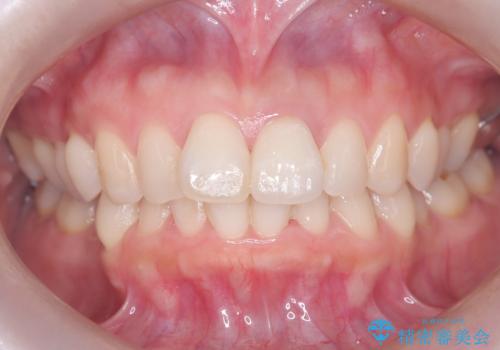

前歯の変色を改善し、本来の自然な美しさへ

治療では、変色した歯を形成した後、精密なシリコン印象材で型取りを行いました。この型取りから、患者様の歯の色や形、透明感を忠実に再現したオーダーメイドのオールセラミッククラウンを作製。金属を一切使わないため、アレルギーの心配がなく、歯ぐきの変色も防ぎます。技工士と連携し、天然歯と見分けがつかないほどの自然な仕上がりを追求。機能性と審美性を兼ね備えた、理想的な前歯を取り戻していただけました。